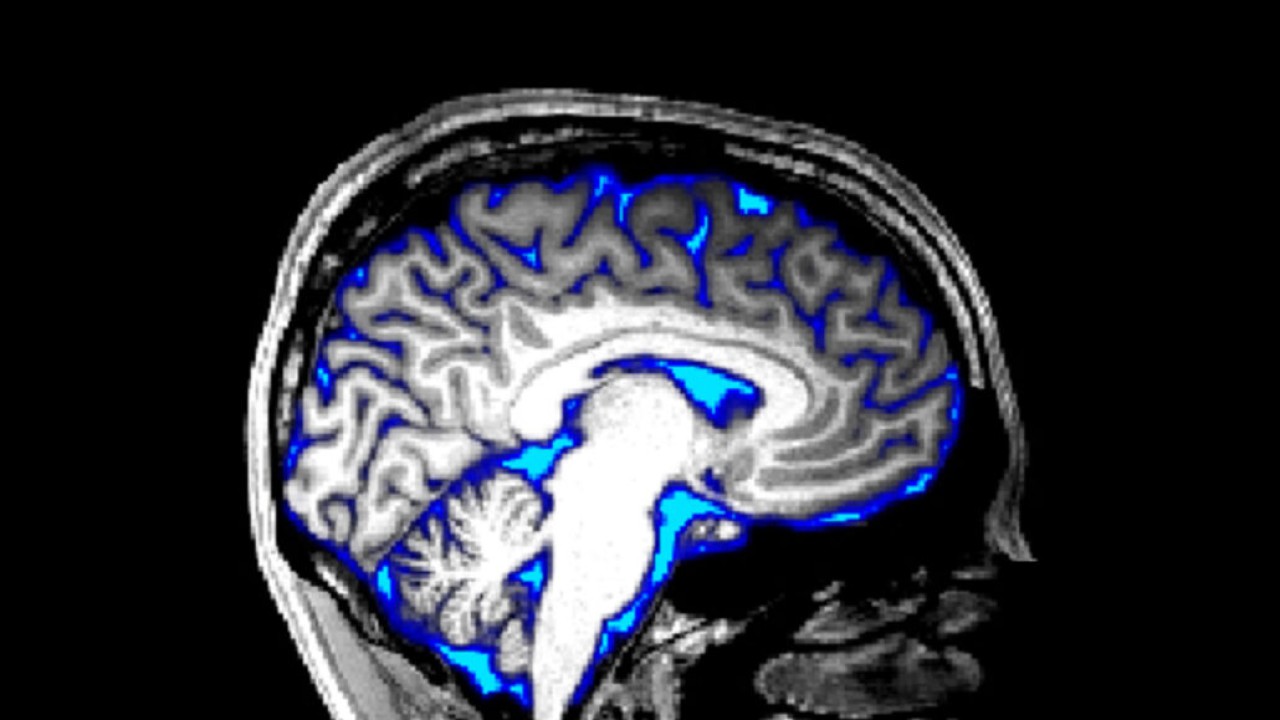

Boston Üniversitesi'nden sinirbilimci Laura Lewis ve meslektaşları, insanların uyurken beyin omurilik sıvısı dalgalarının beynimizi yıkadığını bildirdi ve bu da uykunun bir rolünün beyni derinlemesine temizlemek olabileceği olarak öne sürüldü. Ayrıca ekip, derin, REM dışı uykuyu karakterize eden yavaş nöral salınımların, beyinden geçen omurilik sıvısı dalgalarıyla uyumlu bir şekilde meydana geldiğini gösterdi.

Bu akışlar, kişinin nefes alıp vermesinin ve kalp atışının omurilik sıvısı üzerindeki küçük, ritmik etkilerinden çok daha büyüktü. Araştırmacılar, uyku sırasındaki beyin aktivitesinin beyinden kan akışına neden olarak omurilik sıvısının kafatasının içinde sabit basıncı korumak için kanın arkasına aktığını düşünüyor.